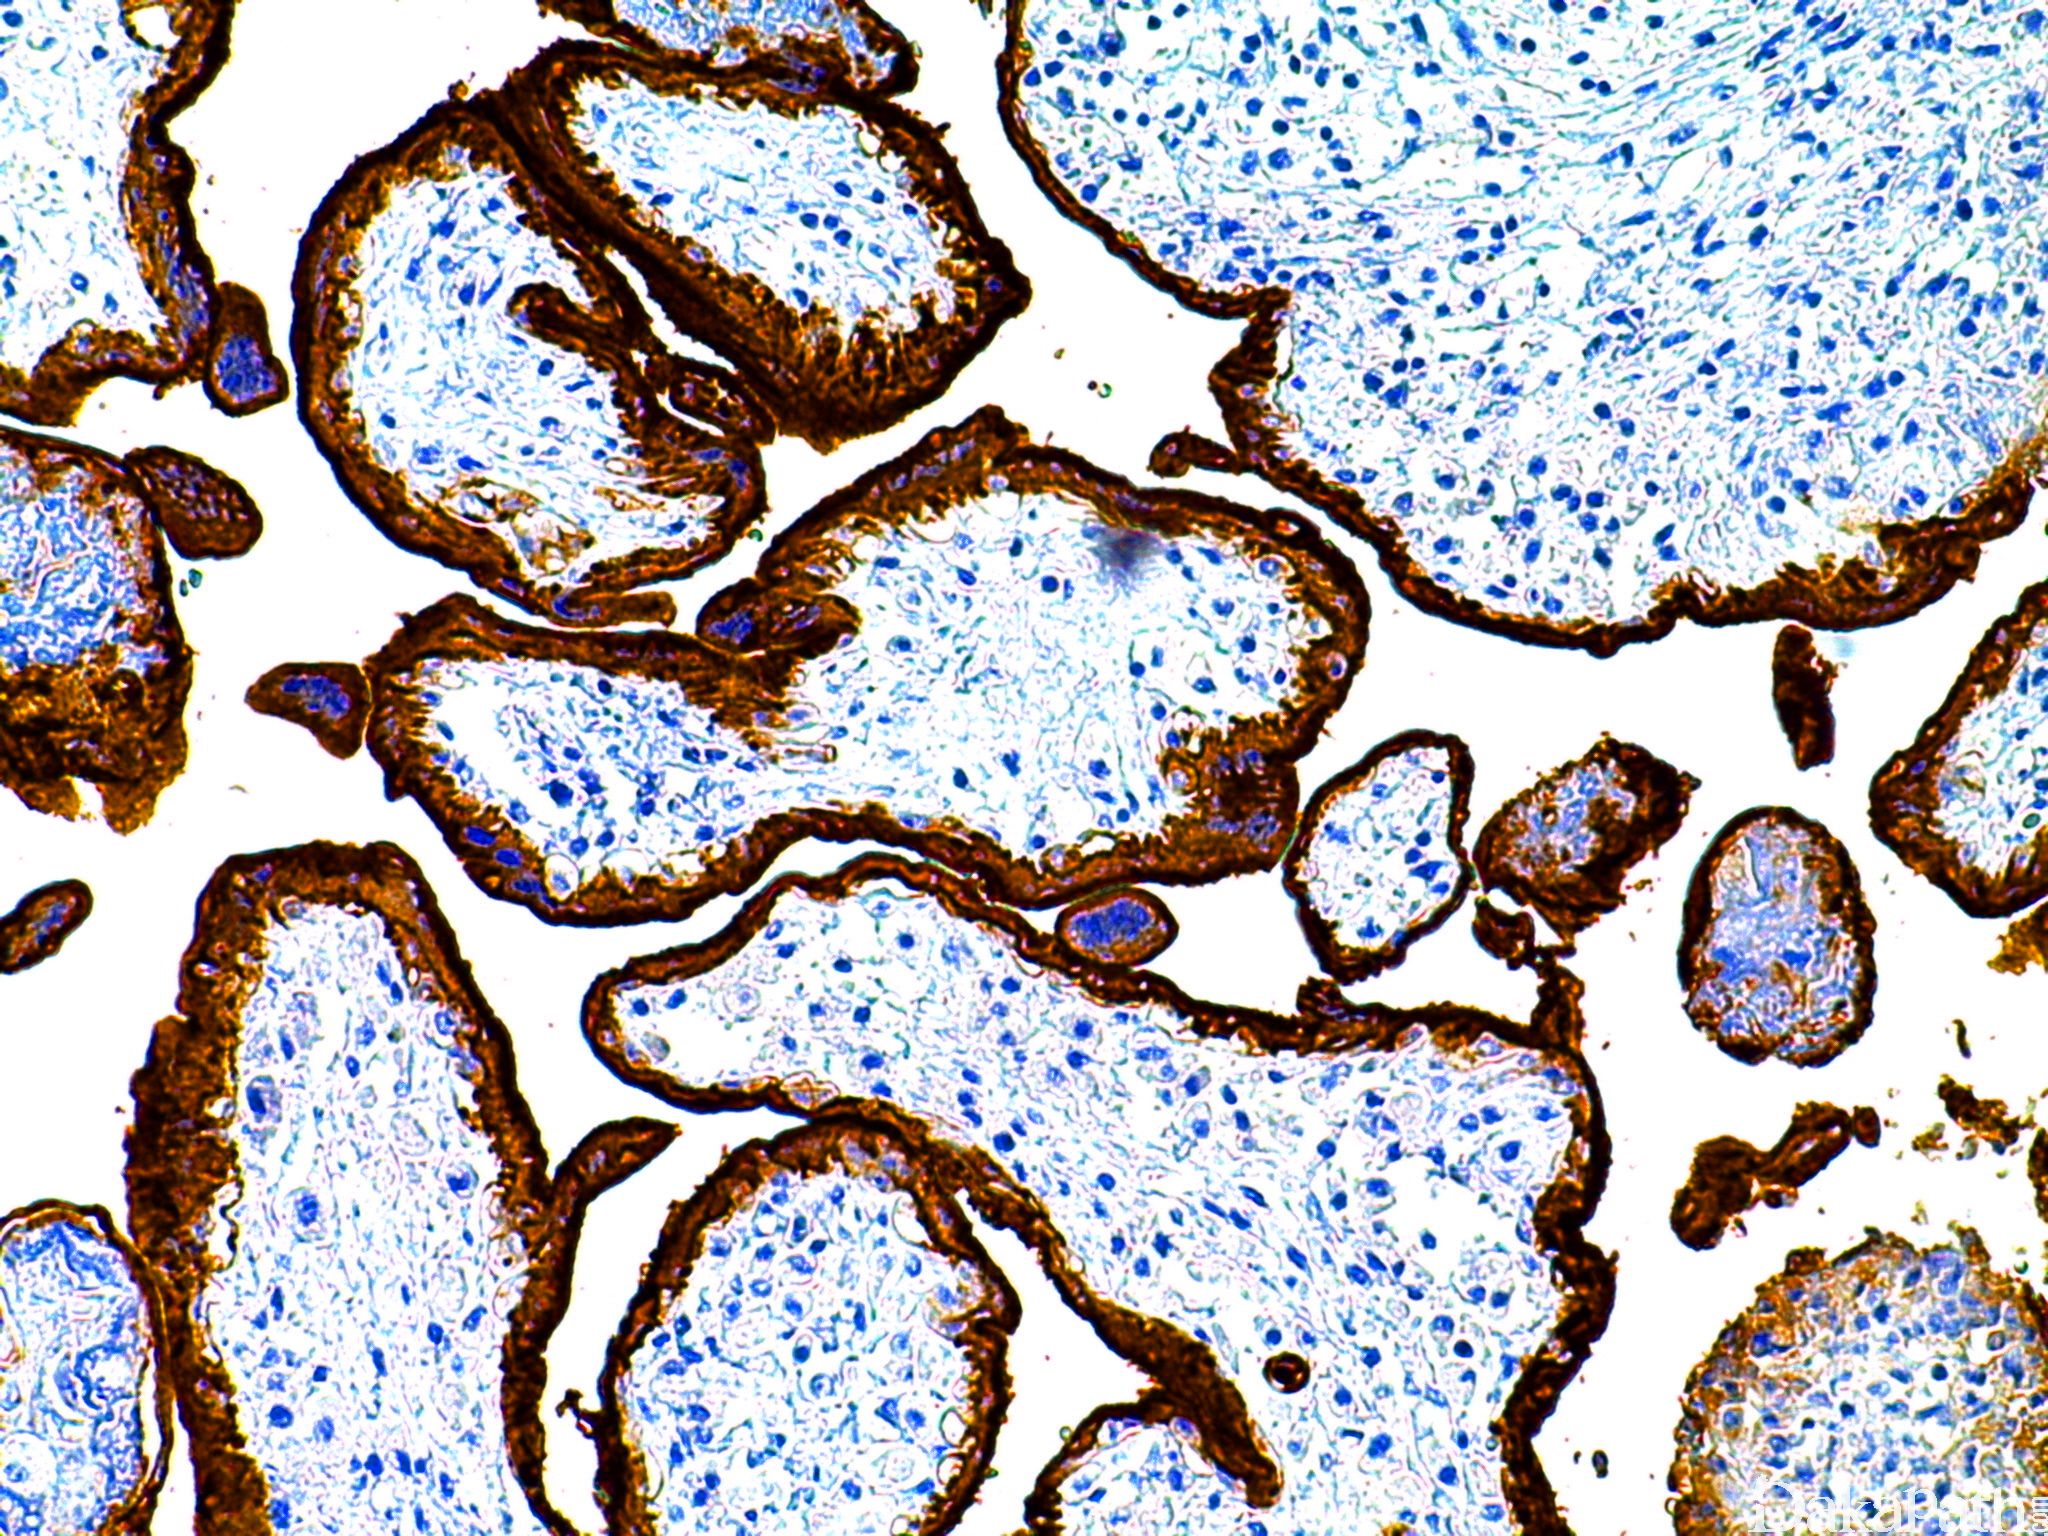

PLAP

胎盘碱性磷酸酶。正常胎盘有表达,可标记生殖细胞肿瘤及肺、胃、胰腺、乳腺和卵巢癌。

信号定位: 胞质

生殖细胞肿瘤的辅助诊断。